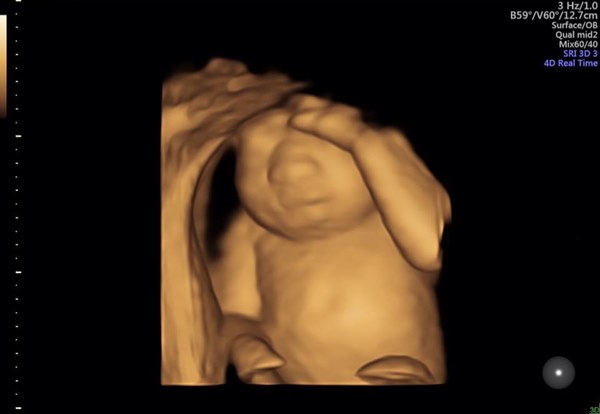

"เธอมีมือเท้าที่สมบูรณ์ มีไต ตับ ปอดที่สมบูรณ์พร้อม แต่น่าเศร้าที่เธอไม่มีสมองที่สมบูรณ์ เราเพิ่งรู้เมื่อไม่นานมานี้ว่าเธอเกิดมาพร้อมสภาวะเด็กกบ" เครี่ โพสต์ในเฟซบุ๊กของเธอ พร้อมกับลงภาพอัลตร้าซาวด์ของลูกน้อย

ภาพจาก เฟซบุ๊ก Royce Young, เฟซบุ๊ก Keri Young